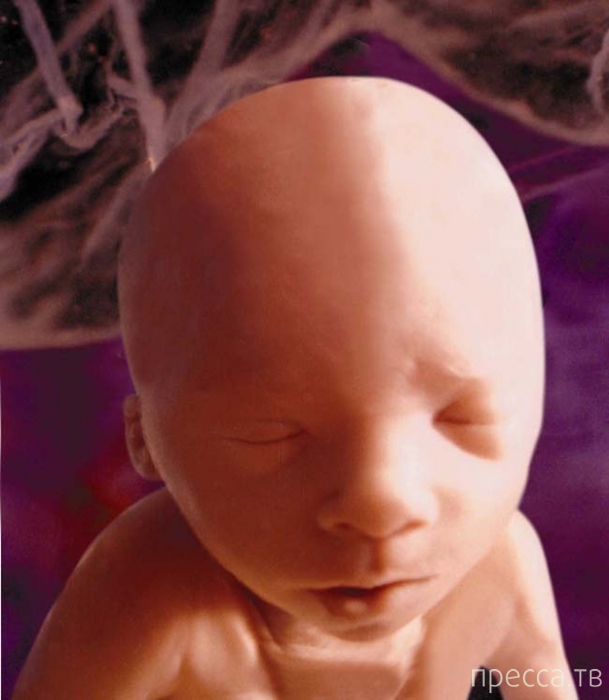

4. Десятая неделя беременности.

Все главные функции организма запущены: почки, кишечник, мозг и печень уже принялись за работу. Ее крошечные ручки и ножки уже начинают сгибаться.

4. Десятая неделя беременности.

Все главные функции организма запущены: почки, кишечник, мозг и печень уже принялись за работу. Ее крошечные ручки и ножки уже начинают сгибаться.